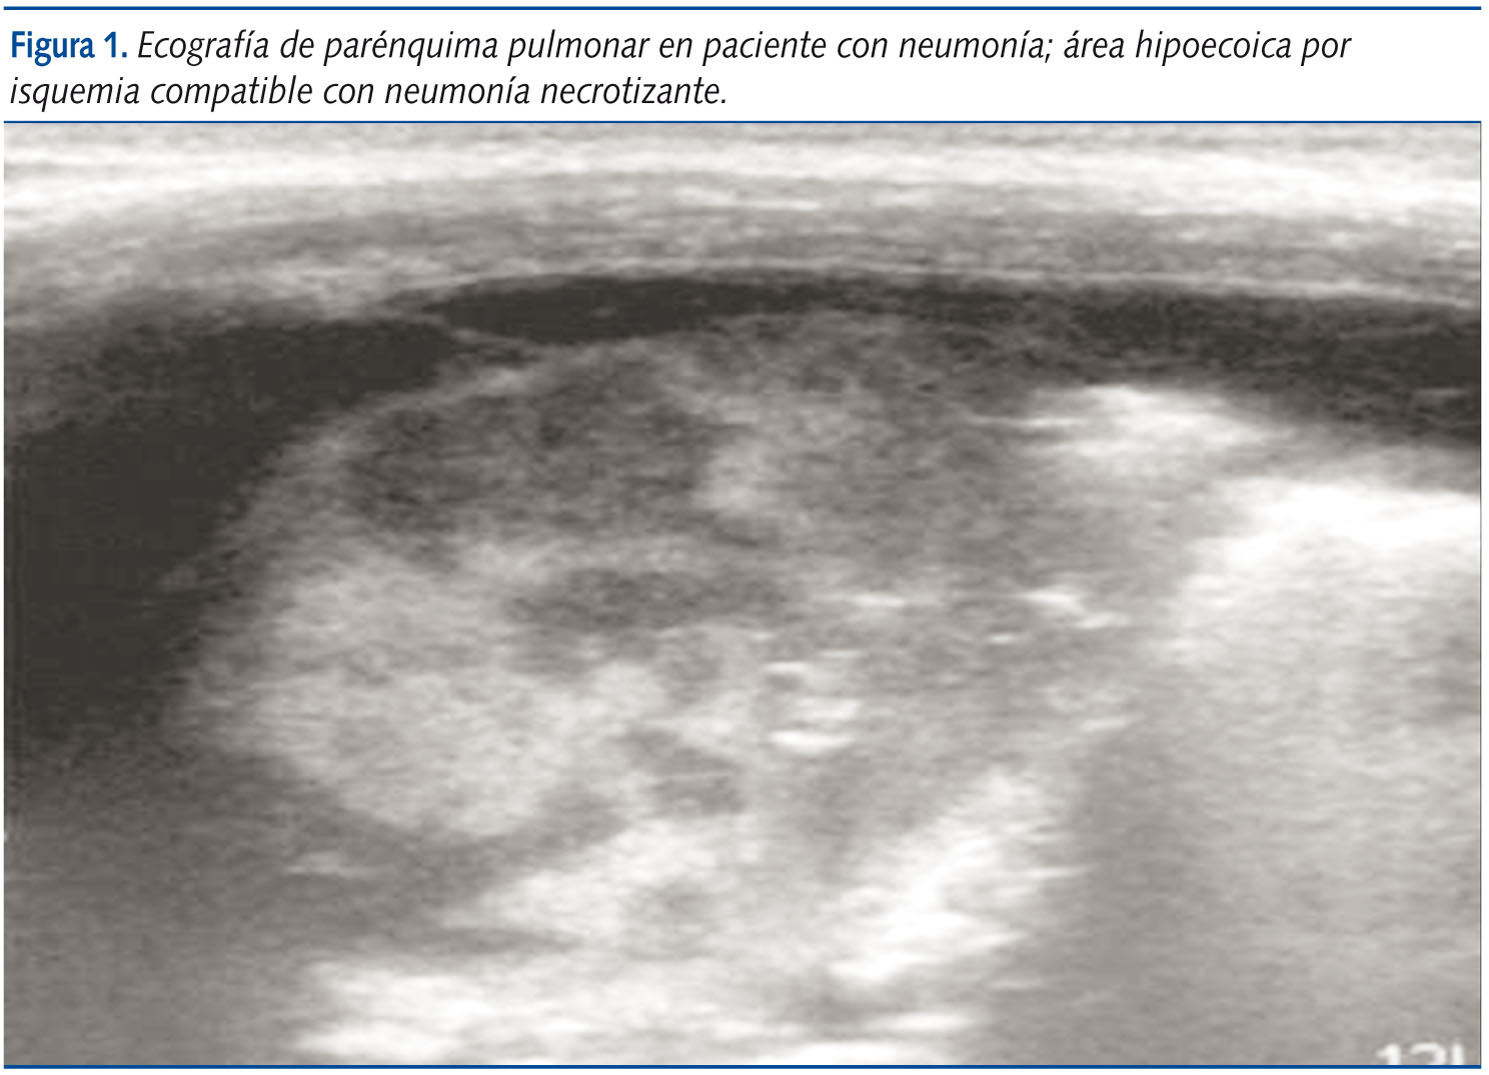

Prácticamente desaparecido el Haemophilus influenzae y pérdida la agresividad del Staphilococcus aureus, el Streptococcus pneumoniae8-11 es el agente etiológico de neumonía más frecuente en la edad pediátrica. Durante los últimos 20 años algunas cepas han experimentado una resistencia progresiva con aparición de serotipos de alta agresividad y capacidad necrotizante.

Las lesiones provocadas por el Mycoplasma pneumoniae12 y los virus afectan directamente al epitelio ciliado de la tráquea a los bronquiolos terminales. Los hallazgos están relacionados con el menor tamaño de la luz bronquial, el escaso desarrollo inicial de los sistemas colaterales de ventilación y la mayor capacidad de secreción mucosa del pulmón pediátrico. El resultado es la preponderancia de la hiperinsuflación pulmonar valvular en la bronquiolitis del lactante. Más adelante, los patrones tanto de origen viral como por Mycoplasma pneumoniae muestran predominio de afectación reticular secundaria al edema bronquial y perivascular con áreas de enfisema o atelectasia por tapones mucosos y discretas áreas de alveolización.